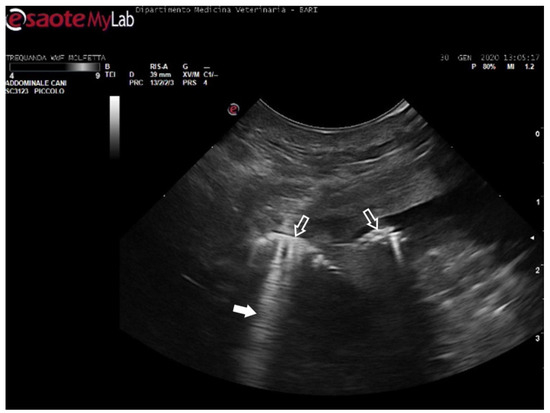

In 11 sea turtles (37, 9%), the ultrasound examination revealed the presence of emboli in various districts, often in limited quantity. Those emboli varied in size but were generally considered microemboli. They were observed to enter the bloodstream in a cascade, resulting in slower and intermittent blood flow on Color Doppler ultrasound. Ultrasonography provided distinct visualization of the liver parenchyma and its vessels, allowing for a clear view of the intestinal loops and their associated circulation. The larger emboli were consistently found adhering to the vessel walls, while smaller emboli occasionally detached and flowed into the bloodstream (Figure 5) (Video S1).

Figure 5.

Ultrasound scan from the right prefemoral window shows an aggregate of medium-sized microemboli adhered to the wall of the iliac vein (white arrow), releasing very small emboli into the bloodstream (empty white arrows). The black arrow indicates the renal parenchyma.

The patients displaying these ultrasound findings were placed in the mild category following Parga’s method [17]. In some animals within this group, ultrasonography revealed emboli in multiple areas compared to those identified on radiographs. Additionally, in a turtle that appeared radiographically negative, ultrasound exams detected the presence of microemboli in the renal arteries on both sides, as well as in the left subclavian artery (Figure 6).